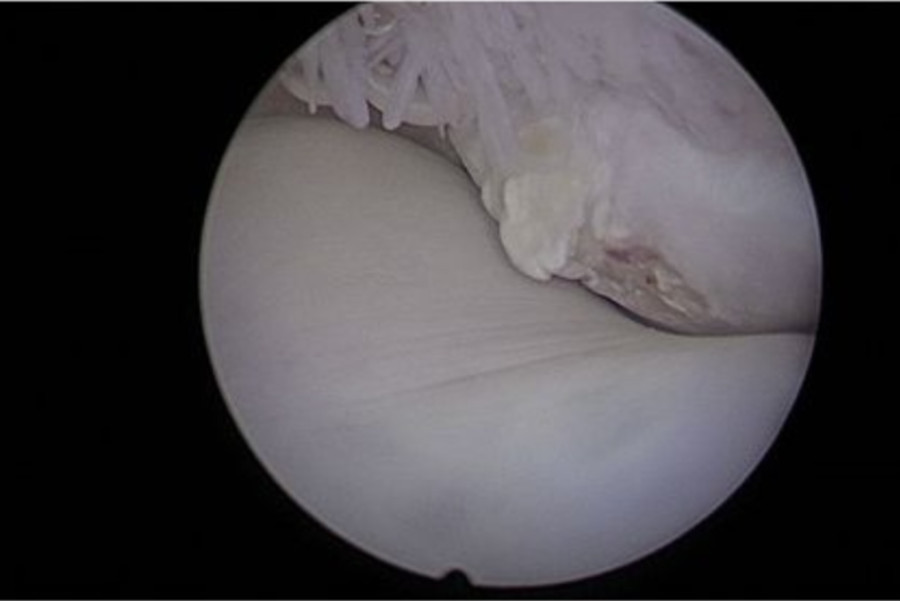

Pour la science on voit bien le bout d'OCD et les lignes de frottement sur l'articulation

(Désolée c'est un screen j'ai pas le cliché en HD)